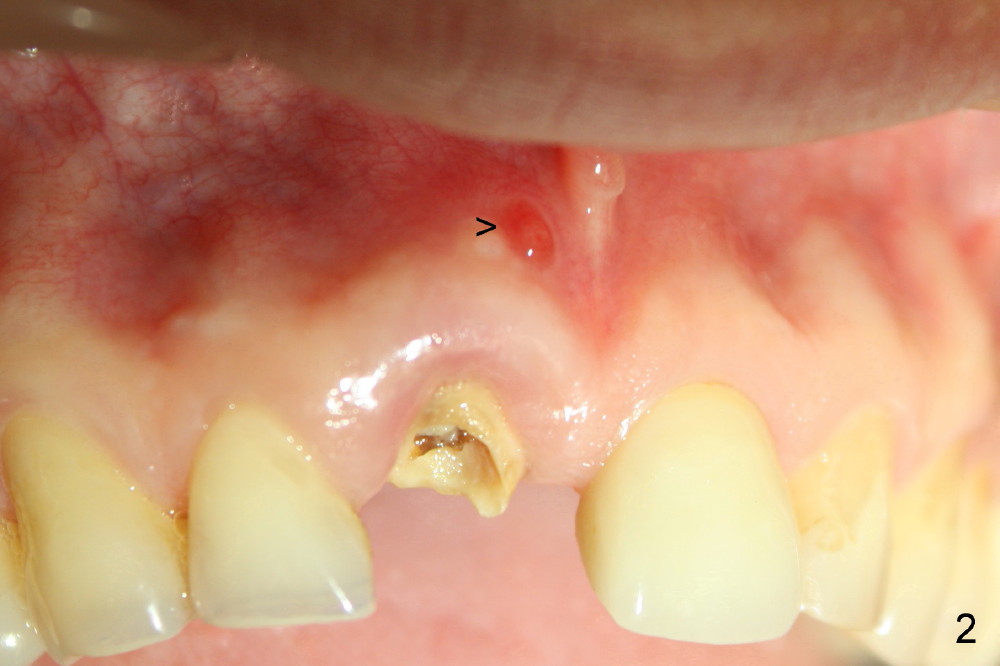

好了,让我们看结果。图三显示即刻植牙,六个月后根尖瘘道消失(图四),愈合基台(healing abutment)近远中牙龈乳头(*)与术前没有多大区别,说明即刻植牙在愈合中维持牙龈外形。今后牙龈谅比正常,我们下次见。